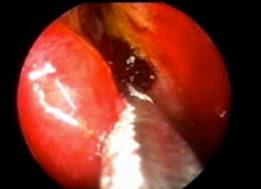

DACRIOCISTORRINOSTOMÍA ENDOCANALICULAR CON LÁSER.

Es la técnica más novedosa. Gracias a unas microfibras de vidrio flexibles que se introducen a través de los puntos lagrimales y canalículos, podemos hacer osteotomías y llegar a la nariz por medio de impulsos de láser.

Es una técnica menos agresiva que las dos anteriores. El inconveniente es la alta tasa de fracasos.

![]() |

| DCR endocanalicular con láser |

Se realiza con anestesia local.

En estos pacientes también se colocan tubos de silicona y se emplea con más frecuencia la Mitomicina.